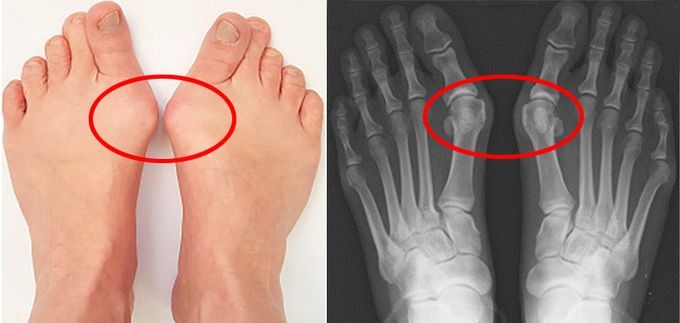

¾öÁö¹ß°¡¶ô ÈÖ´Â ¹«Áö¿Ü¹ÝÁõ, ¼ö¼úÀÌ ´É»ç ¾Æ´Ï´Ù

¹«Áö¿Ü¹ÝÁõÀº ¾öÁö¹ß°¡¶ôÀÌ Èָ鼭 ¹Ù±ùÂÊ °üÀýÀÌ Æ¢¾î³ª¿À´Â ÁúȯÀÌ´Ù. º¸Åë ¼ºÀÎ 4¸í Áß Çϳª 65¼¼ ³ëÀÎÀº 35.7%ÀÇ À¯º´·üÀ» º¸ÀÌ´Â ÈçÇÑ Áúº´ÀÌ´Ù.

¿¬±¸ÆÀÀº ¹«Áö¿Ü¹ÝÁõ ȯÀÚ¸¦ ¾öÁö¹ß°¡¶ôÀÌ ÈÖ¾îÁø °¢µµ¿¡ µû¶ó ¼ÂÀ¸·Î ºÐ·ùÇß´Ù.

¡ãÁßÁõ(40µµ ÀÌ»ó) 25¸í, ¡ãÁߵ(20µµ ÀÌ»ó) 47¸í, ¡ãÁ¤»óÀÎ 36¸íÀ» ´ë»óÀ¸·Î ¹ß¿¡ ¼¾¼­¸¦ ºÙÀÌ°í °ÉÀ» ¶§ ºÐ´ç °ÉÀ½ ¼ö, ¼Óµµ, º¸Æø, º¸°£ µîÀ» ÃøÁ¤Çß´Ù.

±× °á°ú º¸Çà ¼Óµµ¿Í º¸Æø ¹× ¹Ù´ÚÀ» ¹Ð¾î³»´Â ÈûÀº ÁßÁõµµ°¡ ³ô¾ÆÁú¼ö·Ï °¨¼ÒÇß´Ù.

ƯÈ÷ Áߵ ȯÀÚ´Â Áõ»óÀÌ ÀÖ´Â ±×·ì°ú ¾ø´Â ±×·ìÀ¸·Î ³ª´² ºÐ¼®Çߴµ¥ Áõ»óÀÌ ¾ø´Â ȯÀÚ´Â º¸Çà ÀÌ»óÀÌ °ÅÀÇ ³ªÅ¸³ªÁö ¾Ê¾Ò´Ù. Áï Áõ»ó À¯¹«°¡ º¸Çà ÀÌ»óÀ» °áÁ¤ÇÏ´Â °ÍÀÌ´Ù.

µû¶ó¼­ ¿¬±¸ÆÀÀº ¹«Áö¿Ü¹ÝÁõ ¼ö¼ú Ä¡·á ´ë»óÀ» Á¤Çϴµ¥ Áõ»ó ÆÄ¾ÇÀÌ Áß¿äÇÏ´Ù°í ÁöÀûÇß´Ù.

¹«Áö¿Ü¹ÝÁõ ¼ö¼úÀº ¾öÁö¹ß°¡¶ô °üÀý ÁÖº¯ »À¸¦ ÀÚ¸£°í Àδë¿Í °üÀý¸· ¿¬ºÎÁ¶Á÷ ¼ö¼úµµ º´ÇàÇÑ´Ù. À§Ç輺°ú ÇÕº´Áõ ºóµµ°¡ ºñ±³Àû ³ôÀº °ÍÀº ¹°·Ð ¼ö¼ú ÈÄ ¸¸Á·µµ°¡ ȯÀÚ¸¶´Ù Â÷À̸¦ º¸ÀδÙ.

À̵¿¿¬ ±³¼ö´Â ¹«Áö¿Ü¹ÝÁõ ÁßÁõµµ¿¡ µû¶ó ½ÇÁ¦ º¸Çà ÀÌ»óÀ» °´°üÀûÀÎ °Ë»ç·Î Áõ¸íÇÑ ¿¬±¸¶ó¸ç ¹«Á¶°Ç ¼ö¼úÀ» ÇÏÁö ¸»°í ÁõÁõµµ ¹× Áõ»ó À¯¹«¿¡ µû¶ó ½ÅÁßÈ÷ °áÁ¤ÇØ¾ß ÇÑ´Ù°í ¸»Çß´Ù.

ÀÌ¾î ¹«ºÐº° ¼ö¼úÀº µµ¿òÀÌ µÇÁö ¾ÊÀ¸¸ç Ä¡·á ¸¸Á·µµ°¡ ¶³¾îÁú ¼ö ÀÖ´Ù. Àü¹®ÀÇÀÇ Á¤È®ÇÑ Áø´Ü°ú ƯÈ÷ ¼ö¼úÀû Ä¡·áÀÇ ´ë»ó ¿©ºÎ¸¦ ¹Ýµå½Ã È®ÀÎÇÒ Çʿ䰡 ÀÖ´Ù°í µ¡ºÙ¿´´Ù.